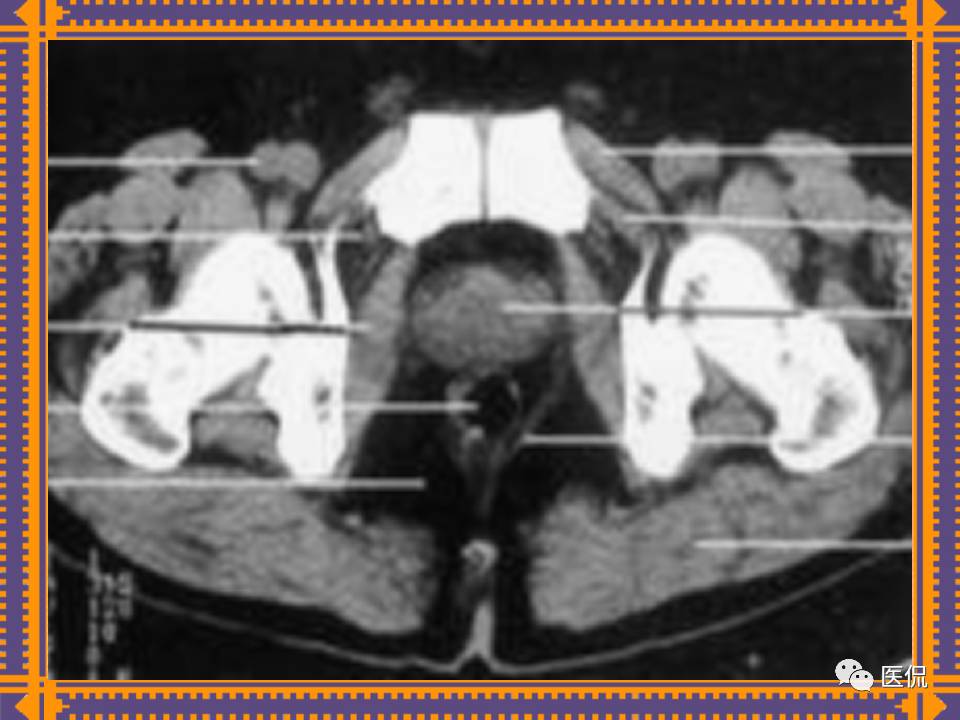

这篇PPT对男性生殖系统疾病:前列腺增生、前列腺癌;女性生殖系统疾病:子宫肌瘤、子宫癌、卵巢囊肿和卵巢肿瘤以及腹膜后间隙疾病进行了详细讲解。